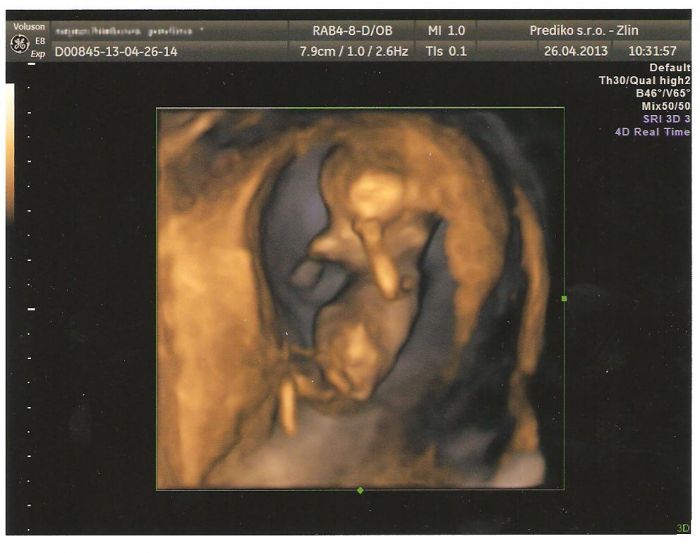

Autor: KlaraN 26.4.2013 v 10:16

Já jsem právě nevěřila mému doktorovi, protože mi zanedbal jedno vyšetření a já jsem měla strach, tak jsem si to sice musela zaplatit, ale vůbec toho nelituji, ultrazvuk na Genetice v Českých Budějovicích a můžu to všem jen doporučit, protože to co zkoumali tam, mi nikdy doktor nedělal, měřily průměr, hlavy, bříška, nožiček, na rty se mi koukaly, jestli nemá roštěp, prohlížely mi srdíčko jestli má všechny komory, no byla jsem naprosto v šoku a zároveň šťastná.